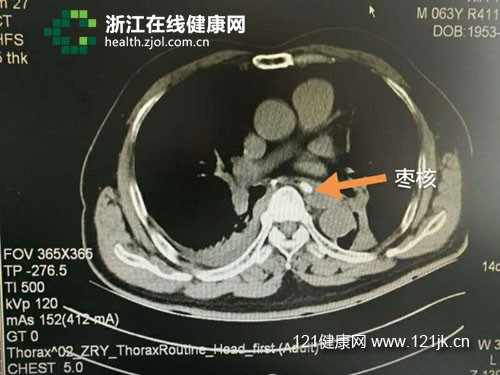

CT片上的枣核,红箭头所指的小亮点

浙江省人民医院心胸外科主任医师朱理、王海涛给徐大伯做了手术。在胃镜协助定位下,专家清楚看到食道中段处(医学上称距隆突下1~2公分处)有两公分多长的枣核卡顿,随即将之取出。

“胸部纵隔处有很多从心脏出来的大血管,枣核一旦刺破大血管就会有生命危险。”王海涛指着取出来两头尖锐的枣核说。